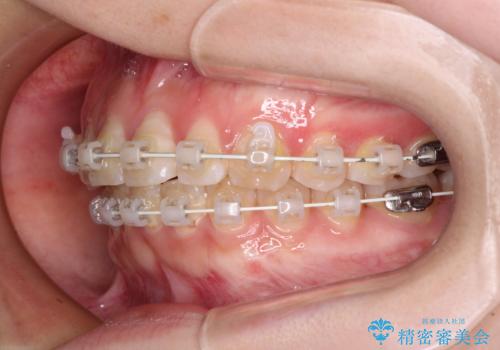

【モニター】前歯のデコボコを目立たないワイヤー装置で短期間矯正治療

- 上下前歯のデコボコを気にして来院された患者様です。

ワイヤー矯正でもインビザライン矯正でも対応可能でしたが、インビザラインでの自己管理の煩わしさを避けるため、ワイヤー装置にて矯正治療を行うこととしました。

患者様も驚く、僅か10か月での治療終了となりました。

下顎前歯が1歯欠損しているため、上下正中は合わず、左右奥歯の咬み合わせは理想的とはならない仕上がりとなります。